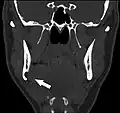

Stafne bone cavity seen on coronal CT

Stafne bone cavity seen on axial CT

Stafne's defect is usually discovered by chance during routine dental radiography.[11] Radiographically, it is a well-circumscribed, monolocular, round, radiolucent defect, 1–3 cm in size, usually between the inferior alveolar nerve (IAN) and the inferior border of the posterior mandible between the molars and the angle of the jaw. It is one of the few radiolucent lesions that can occur below the IAN. The border is well corticated and it will have no effect on the surrounding structures. Computed tomography (CT) will show a shallow defect through the medial cortex of the mandible with a corticated rim and no soft tissue abnormalities, with the exception of a portion of the submandibular gland. Neoplasms, such as metastatic squamous cell carcinoma to the submandibular lymph nodes or a salivary gland tumour, could create a similar appearance but rarely have such well defined borders and can usually be palpated in the floor of the mouth or submandibular triangle of the neck as a hard mass. CT and clinical exam is typically sufficient to distinguish between this and a Stafne defect. The Stafne defect also tends to not increase in size or change in radiographic appearance over time (hence the term "static bone cyst"), and this can be used to help confirm the diagnosis.[11] Tissue biopsy is not usually indicated, but if carried out, the histopathologic appearance is usually normal salivary gland tissue. Sometimes attempted biopsy of Stafne defects reveals an empty cavity (possibly because the gland was displaced at the time of biopsy), or other contents such as blood vessels, fat, lymphoid or connective tissues. Defects of the anterior lingual mandible may require biopsy for correct diagnosis at this unusual location.[5] The radiolucent defect here may be superimposed on the lower anterior teeth and be mistaken for an odontogenic lesion. Sometimes the defect may interrupt the contour of the lower border of the mandible, and may be palpable. Sialography may be sometimes used to help demonstrate the salivary gland tissue within the bone.